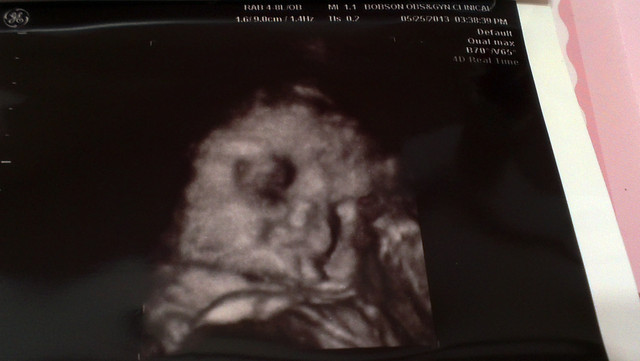

20121201去產檢的時候,發現小章魚已經成形囉

整個身體和頭都發展得很好

已經出現人的形狀了

感覺好特別

每天都在變化耶

而且這時已經滿3個月囉

終於過了安全期

而且這時的小章魚脊髓已經成形了

看看超音波照的好清楚

骨骼發育也很好